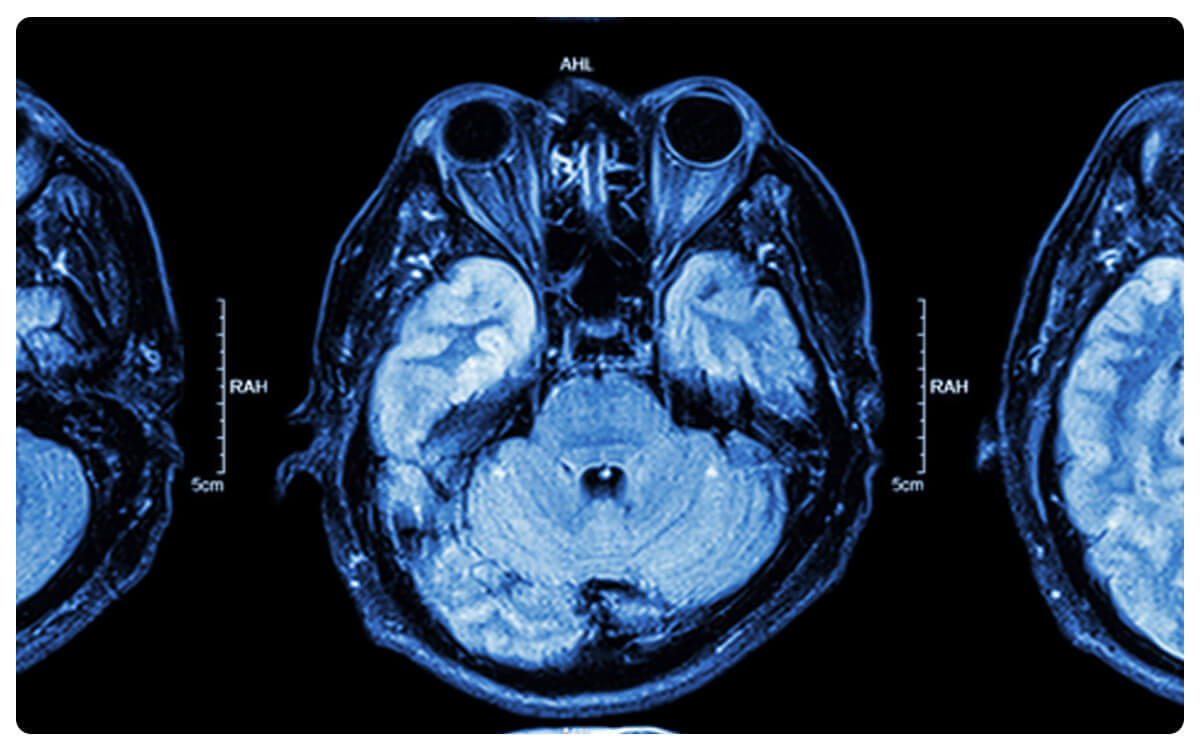

La Tomografía Multicorte (MC) de órbita Simple y Contrastada, una técnica de imagen médica avanzada, se posiciona como una herramienta esencial en la exploración detallada y precisa de las estructuras orbitales del ojo.

A través de la tomografía computarizada y la administración de un medio de contraste intravenoso, esta técnica permite la obtención de imágenes tridimensionales de alta resolución que revelan la anatomía ocular y posibles afecciones en las orbitas.

La Tomografía MC de órbita Simple y Contrastada desempeña un papel crucial en el diagnóstico y seguimiento de enfermedades oculares y periorbítales, proporcionando información valiosa para la detección temprana de trastornos y la toma de decisiones clínicas informadas en el cuidado de la salud ocular.